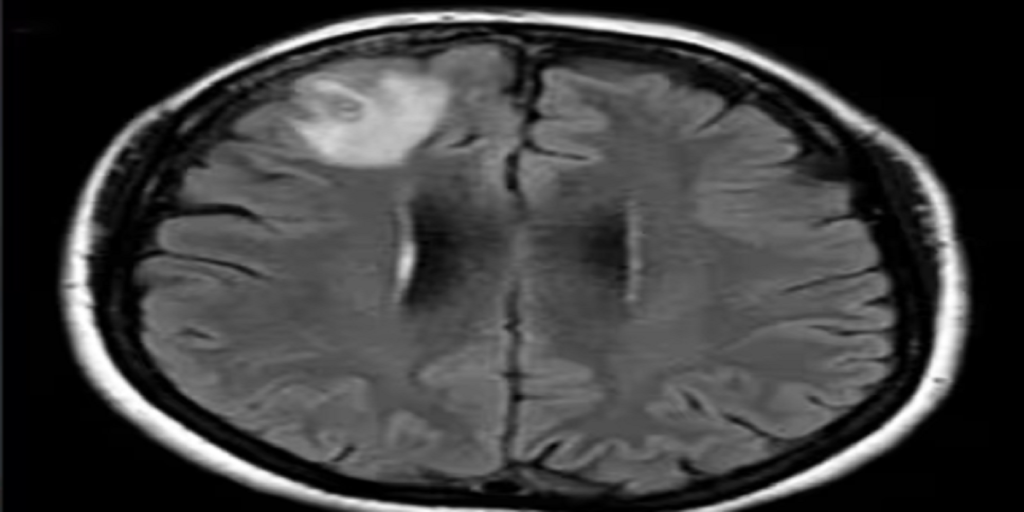

Udland Kvinde led af glemsomhed og depression: Så gør lægerne chokerende fund i hendes hjerne Nicolai Steinicke • 29. august 2023